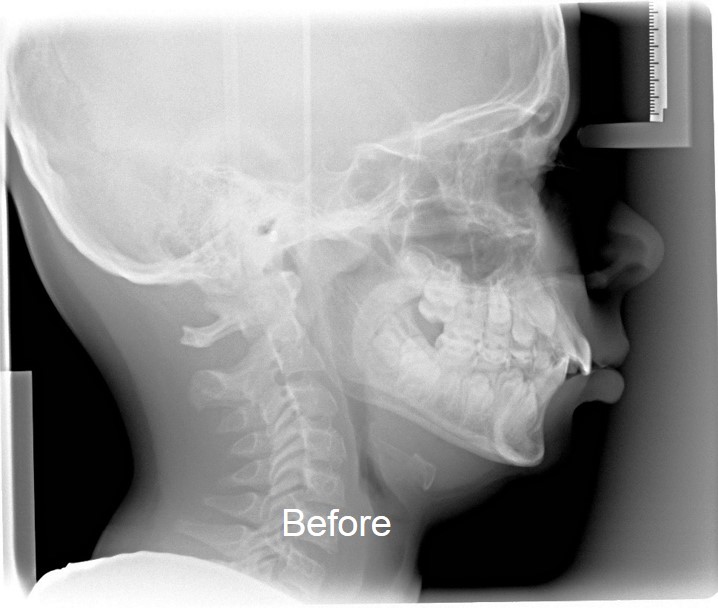

The world renown inventor and developer of the dental treatment system, that straightens teeth without braces and treats health issues related to SDB, has created a safe, all natural, pro-active, drug-free and pain-free oral appliance that delivers permanent results when started early and worn with compliance.

For nearly 50 years, HealthyStart™ devices, worn mainly at night while children sleep, have been effectively correcting the restricted airway conditions in young children, caused by what is now referred to as Sleep Disordered Breathing, SDB.

20 years of research has now connected Sleep Disordered Breathing to over a dozen health-limiting conditions.  Parents battle a ticking clock to open the restricted airway associated with crooked teeth, bed wetting, diminished growth, challenged academics, snoring, mouth breathing and a dozen other symptoms. Puberty marks the finish line to the growth phase needed for the correction HealthyStart™ Dental Appliances bring to the 9 out of 10 children challenged with health issues and the potential for lifelong complications.

The options for many of those left untreated by the time they reach their teenage years, may include tooth extractions to provide space for adult teeth and then years in braces to align them.  Traditional orthodontic treatment does not address a compromised airway and braces generally come with some expected degree of relapse.